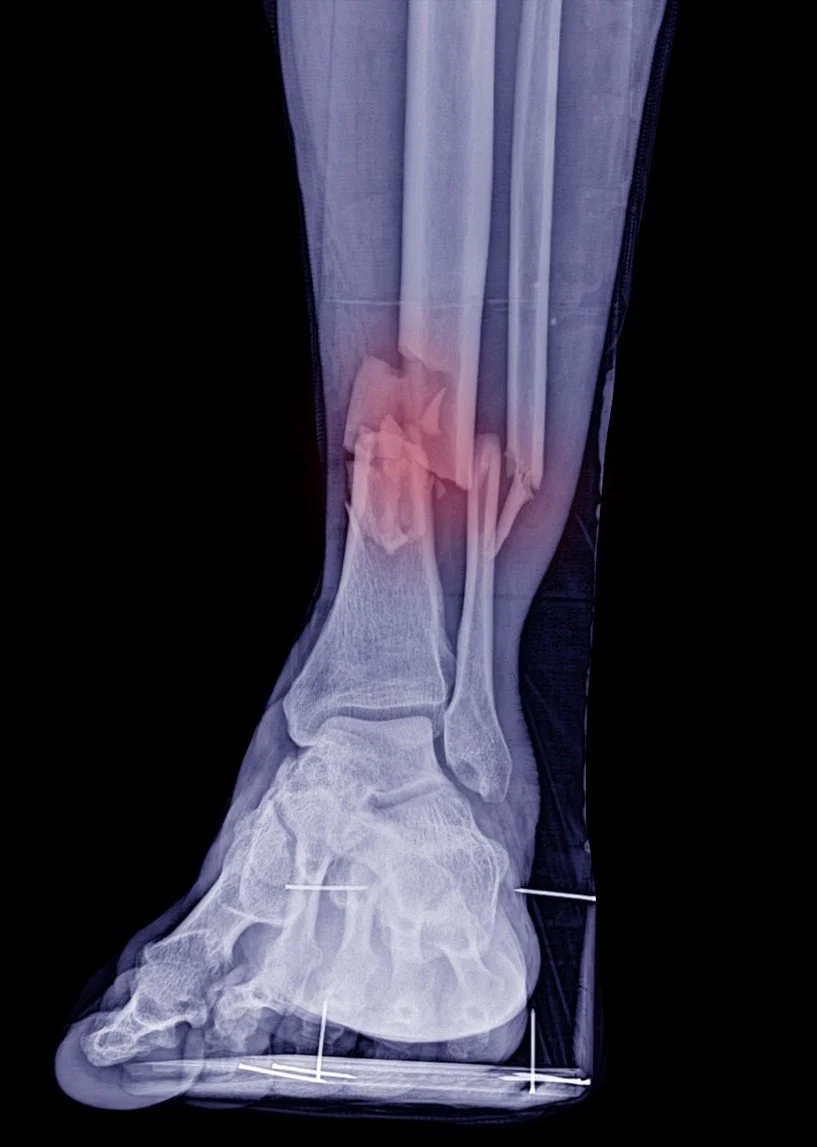

Allan, a warehouse worker in Western Sydney, suffered a serious ankle injury after a forklift accident. Initial delays in treatment and communication left him anxious about his recovery and his job security. The employer, facing rising premiums from a previous poorly managed claim, engaged Caliso as their RTW Coordinator to avoid further increased costs and ensuring additional support for Allan.

Caliso acted quickly — coordinating with Allan and his GP, setting clear recovery goals, ensuring Allan knew what to expect and implementing modified duties. Allan returned part-time within four weeks (rather that the initial estimate of 12 weeks) and resumed full duties after four months.